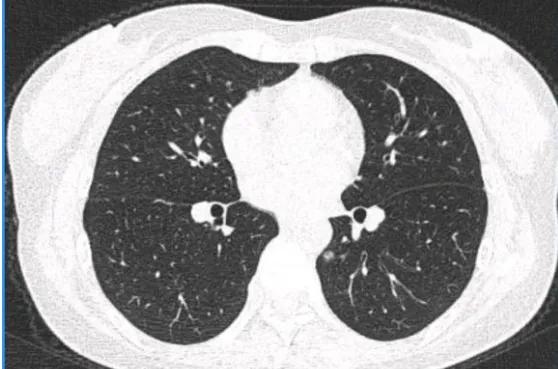

戴主任,您好!很遺憾現在才知道您,要不然也不會這樣焦慮。本人,女,43歲,於2020年10月單位體檢,發現磨玻璃結節後一直隨訪,大小、形態也沒有變化。最後一次2021年11月檢查時大夫讓做手術,說位置不好需切肺葉。由於對切肺葉接受不了,上北京求診,先後去過協和、東腫胸外科。協和說切,東腫說可以繼續觀察,如果切除要段切,甚至葉切。由於治療心切,又不想葉切,在心慌意亂之下選擇了消融,也沒有病理。可深入瞭解消融,又開始後怕,整夜睡不著覺。懇請戴主任百忙之中,看一下我的片子是什麼性質?磨玻璃如果復發會怎麼樣?是磨玻璃結節,還是會變成別的?會不會惡性程度高了?現在,有什麼補救措施嗎?懇請您百忙之中,能回覆,百分感謝。

這個是微浸潤腺癌,精準定位下,其實楔形切除小手術即可根治。目前建議定期隨訪,密切關注消融後病灶的變化情況,不長大就安全。萬一長大也可以再手術。